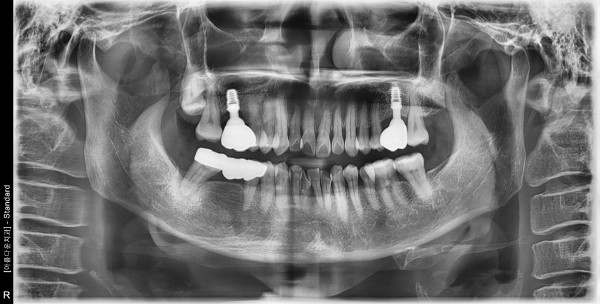

62세 여자 상악 양측 구치부 발치, 치조골이식술 후 임플란트 식립